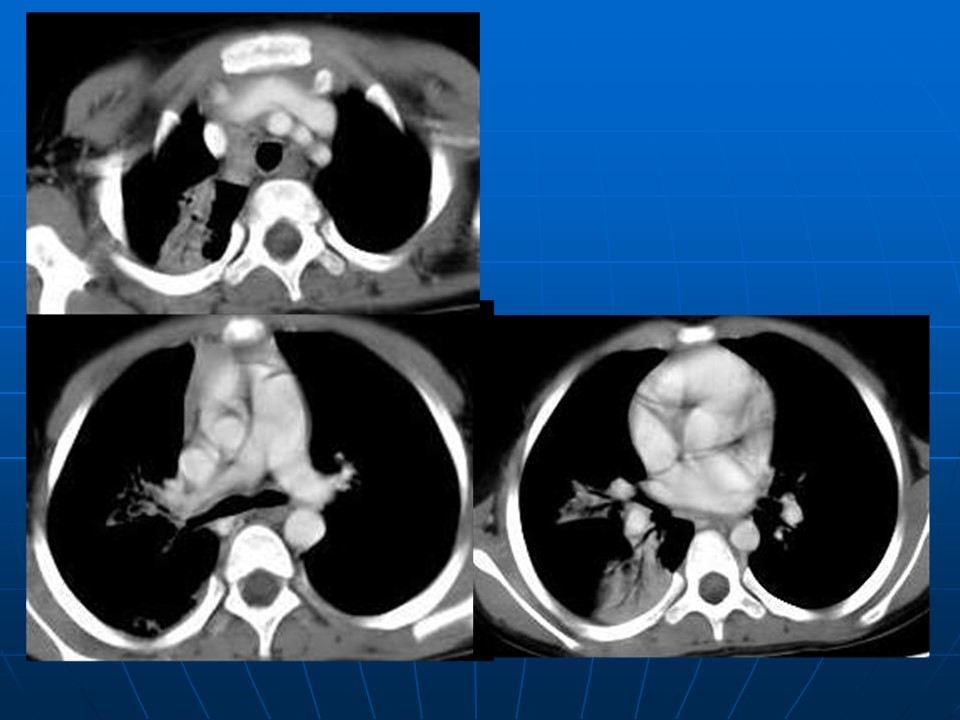

下一篇:【病例】肺动脉静脉畸形1例CT